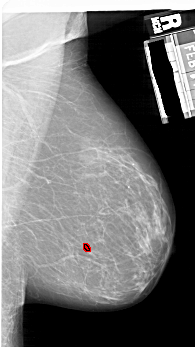

A_1925_1.LEFT_MLO

LEFT_MLO LINES 6406 PIXELS_PER_LINE 3586 BITS_PER_PIXEL 12 RESOLUTION 43.5 NON_OVERLAY

FILE: A_1925_1.RIGHT_MLO.OVERLAY

TOTAL_ABNORMALITIES 1

ABNORMALITY 1

LESION_TYPE CALCIFICATION TYPE PLEOMORPHIC DISTRIBUTION CLUSTERED

ASSESSMENT 4

SUBTLETY 3

PATHOLOGY BENIGN

TOTAL_OUTLINES 1

BOUNDARY